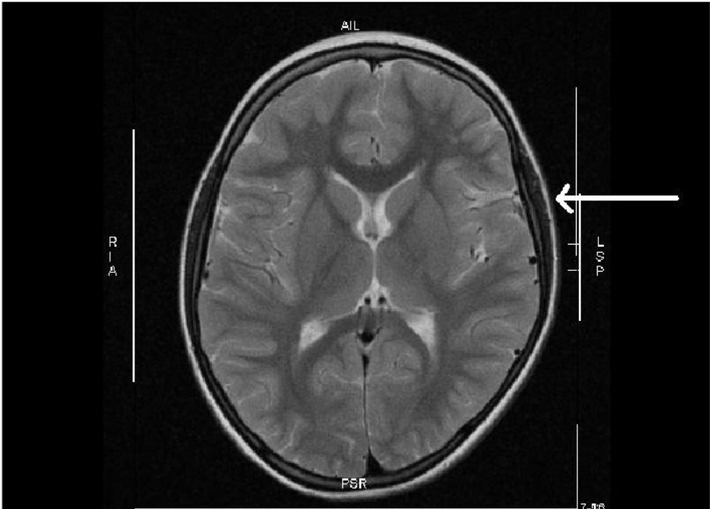

Ein Heilversuch mit Stammzellen bei Schlaganfall nach der Geburt wies den Weg

In einer kürzlich erschienenen Publikation hatte ein kleines Mädchen unter der Geburt einen Schlaganfall mit Halbseitenlähmung erlitten, obwohl es am Termin nach unauffälliger Schwangerschaft der Mutter mit normalen Apgar-Werten bei großem Kopfumfang (> 97. Perzentile) und Anzeichen einer starken Kopfverformung scheinbar gesund geboren worden war. Nach der Magnetresonanz-Tomographie des Schädels (MRT), die einen wegweisenden Befund ergab, wurde die Stammzellbehandlung aus Nabelschnurblut erfolgreich durchgeführt. "Zu unserer Überraschung war die Druckstelle am Gehirn durch die mechanische Kompression 5 Jahre nach der Geburt des Mädchens immer noch sichtbar", erinnert sich Prof. Arne Jensen. "Wir haben daraufhin unsere Datenbank gezielt durchsucht und festgestellt, dass bei Kombination von großem kindlichen Kopfumfang mit protrahierter Geburt oder Geburtsstillstand ein hohes Risiko für eine Hirnschädigung in der weißen Substanz besteht."